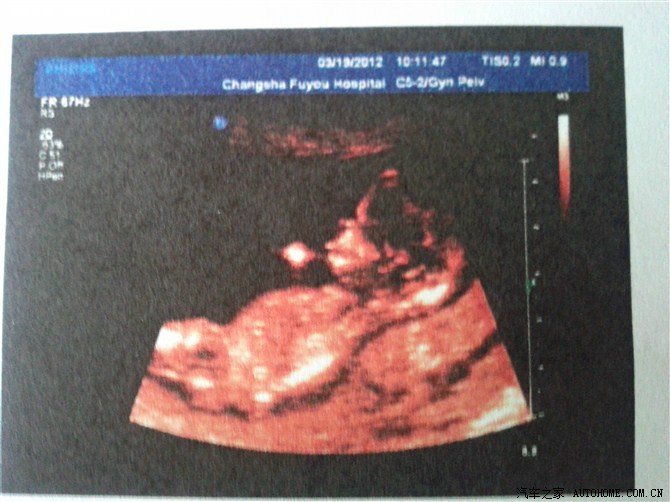

13周时的四维彩超